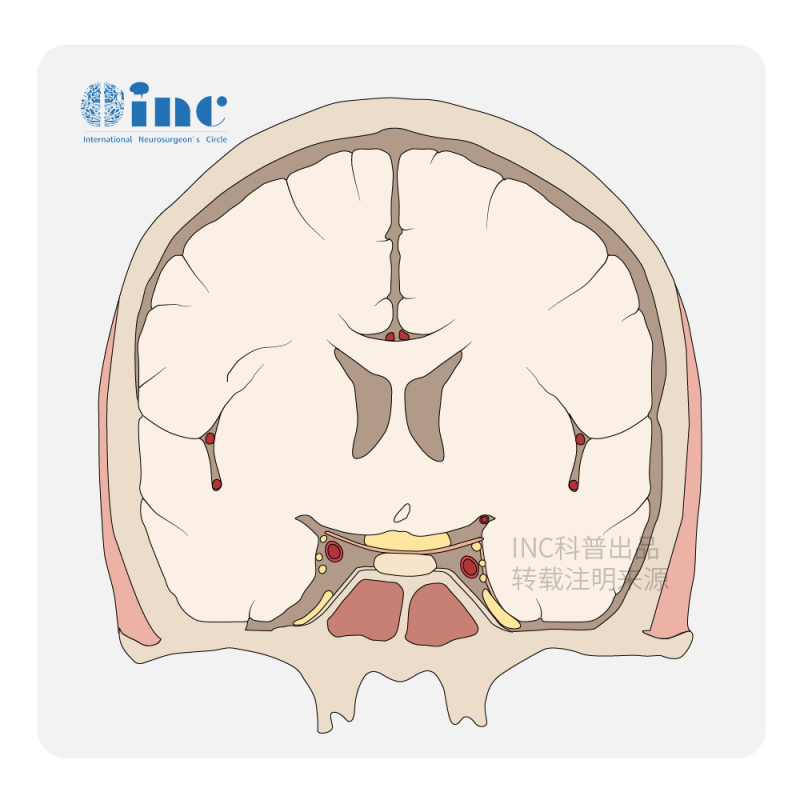

腦膜瘤的臨床表現(xiàn)有哪些?腦膜瘤是來(lái)源于包裹蛛網(wǎng)膜的腦膜上皮細(xì)胞的腫瘤。因此,發(fā)生在腦實(shí)質(zhì)外的腦膜瘤是軸外腫瘤。女性比男性更常見,65%的確診...